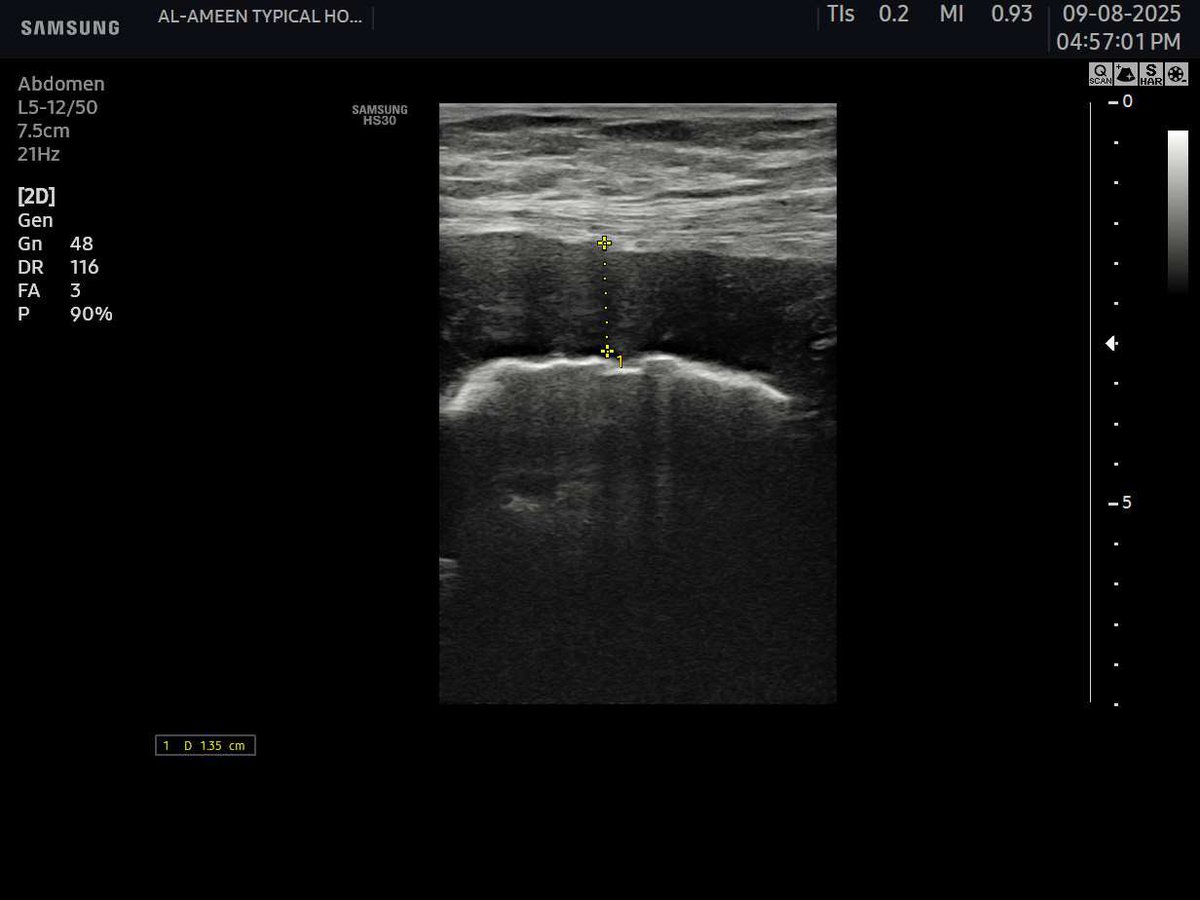

𝗖𝗘𝗥𝗩𝗜𝗖𝗔𝗟 𝗟𝗘𝗡𝗚𝗧𝗛 𝗜𝗡 𝗨𝗟𝗧𝗥𝗔𝗦𝗢𝗨𝗡𝗗 Normal Cervical Length : ≥25 mm Risk starts : <25 mm Serious risk : <15 mm #EchoTech

𝗖𝗘𝗥𝗩𝗜𝗖𝗔𝗟 𝗟𝗘𝗡𝗚𝗧𝗛 𝗜𝗡 𝗨𝗟𝗧𝗥𝗔𝗦𝗢𝗨𝗡𝗗 Normal Cervical Length : ≥25 mm Risk starts : <25 mm Serious risk : <15 mm #EchoTech

𝗖𝗘𝗥𝗩𝗜𝗖𝗔𝗟 𝗟𝗘𝗡𝗚𝗧𝗛 𝗜𝗡 𝗨𝗟𝗧𝗥𝗔𝗦𝗢𝗨𝗡𝗗 Normal Cervical Length : ≥25 mm Risk starts : <25 mm Serious risk : <15 mm #EchoTech